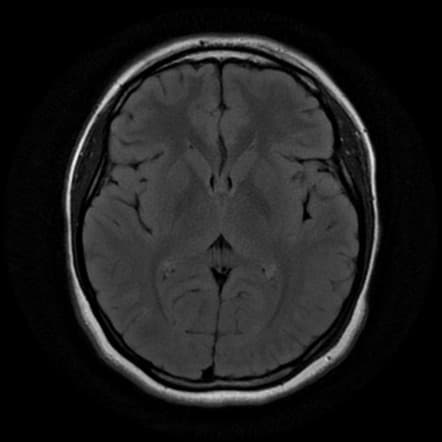

Detect Ischemic Stroke and Vessel Occlusion Using CTA and MRI Scans

Acute Ischemic Stroke (AIS) affects millions of individuals worldwide, with a significant impact on mortality and disability rates. Stroke segmentation plays a crucial role in stroke diagnosis as it enables the identification of the Brain regions affected by stroke. Our automatic 3D segmentation model segments Brain lesions for acute stroke using MRI scan.